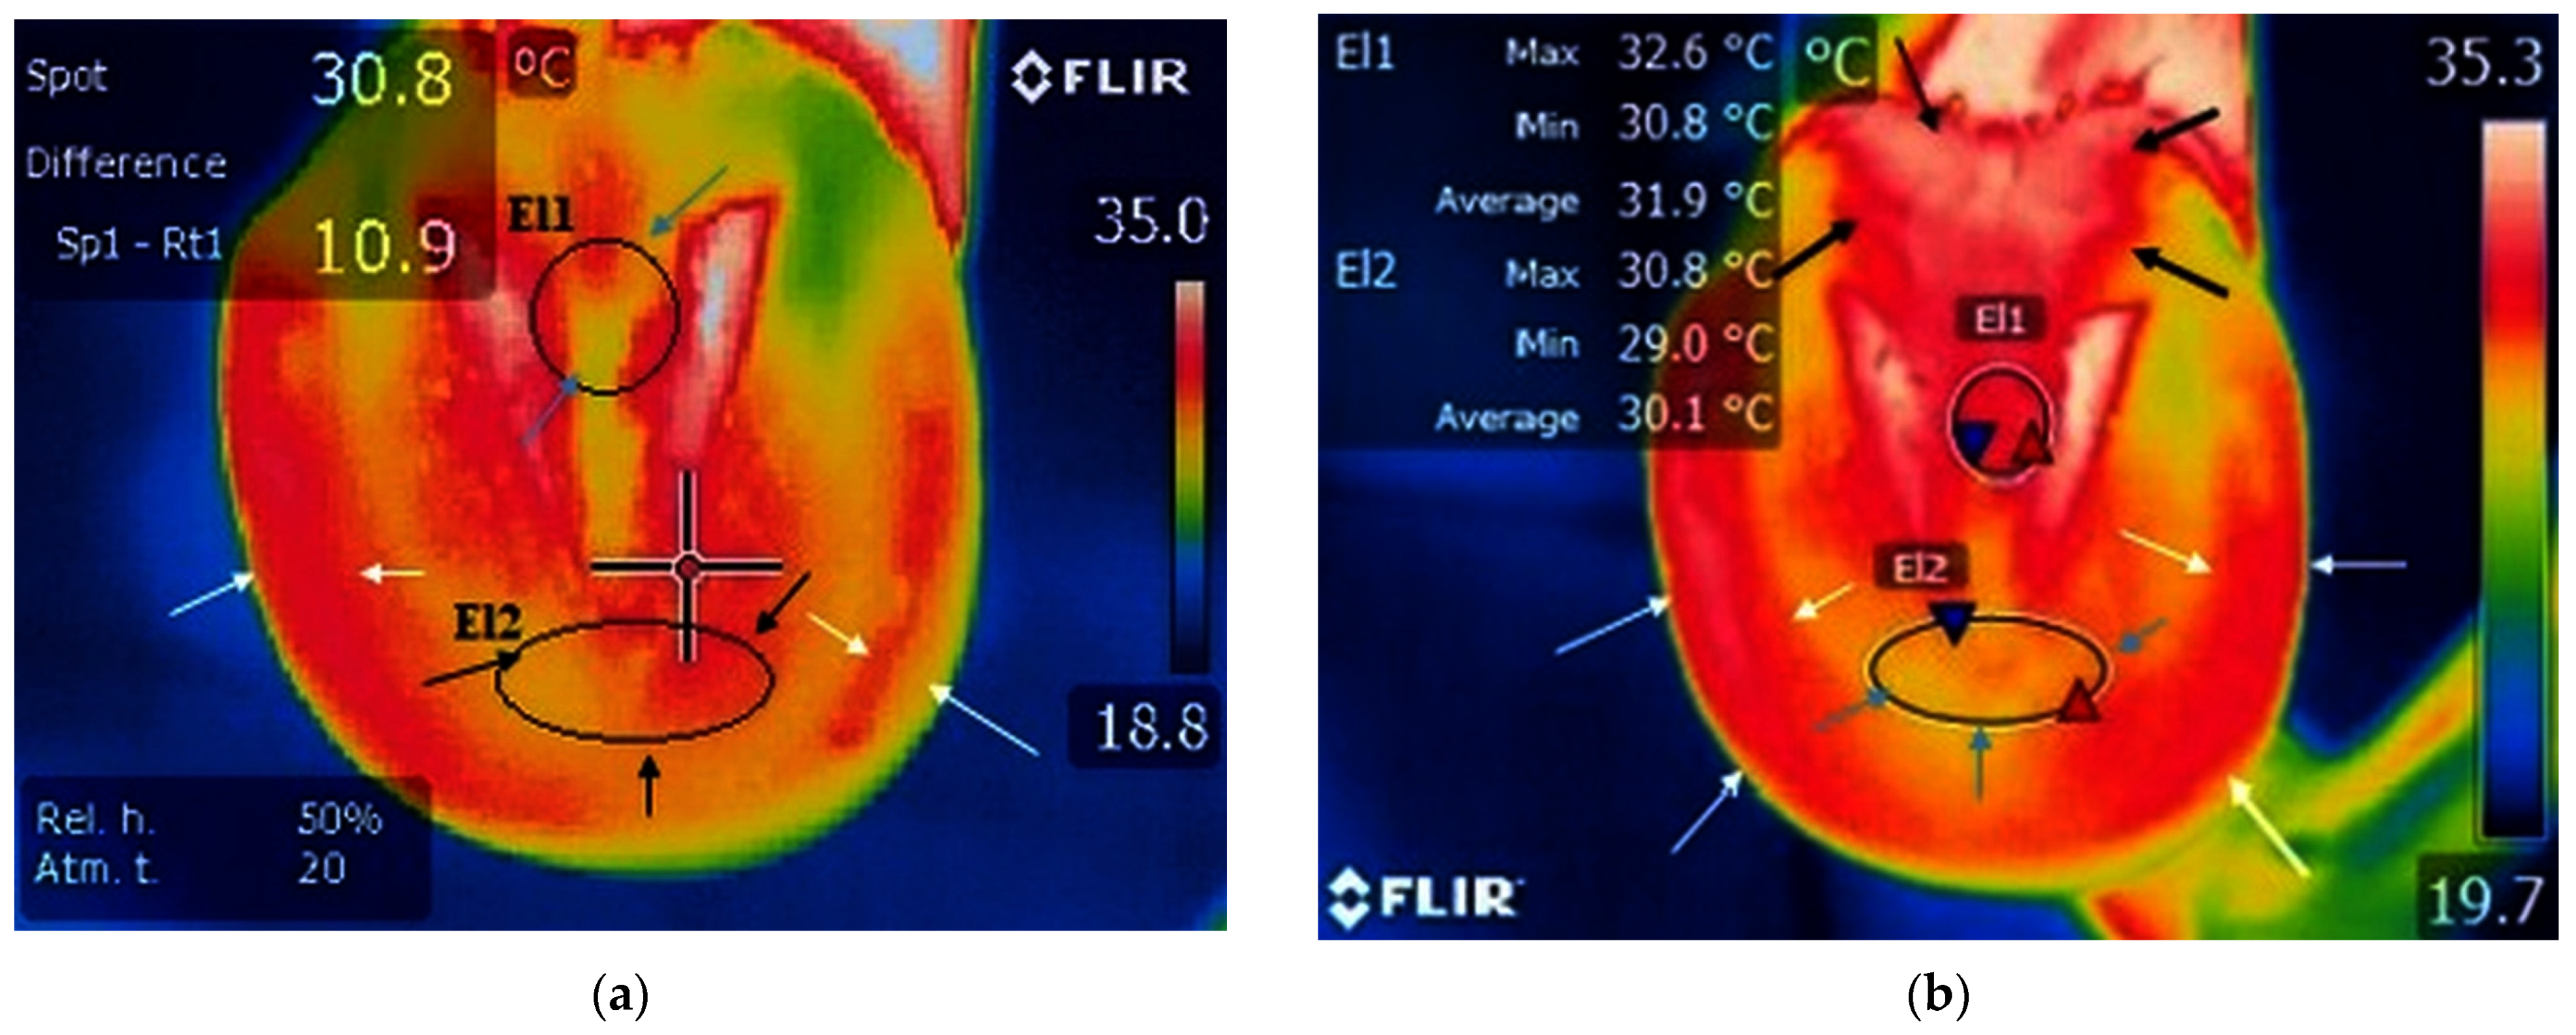

A small area of increased temperature was noticed between the frog and the hoof wall, which corresponds to the toe area, in the study group with palmar foot pain (Figure 3a and Table 1). The m.m.v.t. of the toe area was 20.6 °C.

Figure 3.

Study group, limbs with palmar foot pain: (a) sole surface before training—small surface of increased temperature in the frog area (blue arrows) and toe area (black arrows); reduced temperature along the hoof wall (white arrows); minimum temperature recorded in the area—blue triangle spot; maximum temperature recorded in the area—red triangle spot; (b) sole surface after training—increased temperature and wider surface of increased temperature in the toe area (black arrows); no obvious changes in local temperature in the frog area (blue arrows); increased temperature along the hoof wall (white arrows); minimum temperature recorded in the area—blue triangle spot; maximum temperature recorded in the area—red triangle spot.

A small area of increased temperature was present near the toe in the study group with the contralateral non-lame limb (Figure 4a and Table 1). The m.m.v.t. value of the toe area was 27.7 °C.

Figure 4.

Study group, non-lame limbs: (a) sole surface before training—reduced temperature and small surface of temperature in the frog area (blue arrows); increased area of temperature on hoof wall surface (white arrows); reduced temperature in the toe area (black arrows); (b) sole surface after training—increased temperature and wider surface of increased temperature in the frog area (black arrows); increased surface of temperature along the hoof wall (white arrows); small surface of reduced temperature in toe area (blue arrows); minimum temperature recorded in the area—blue triangle spot; maximum temperature recorded in the area—red triangle spot.

In the case of the control group, the toe area presented limited temperature increases (Figure 5a and Table 1). The m.m.v.t. for toe area was 24.0 °C.

Figure 5.

Control group: (a) small surface of increased temperature in the toe area (black arrows); small surface of increased temperature in the frog area (blue arrows); reduced temperature of the hoof wall (white arrows); minimum temperature recorded in the area—blue triangle spot; maximum temperature recorded in the area—red triangle spot; (b) increased local temperature and wider surface of increased temperature in the toe area (black arrows); increased local temperature and wider surface of increased temperature in the frog area (blue arrows); increased temperature along the hoof wall (white arrows); minimum temperature recorded in the area—blue triangle spot; maximum temperature recorded in the area—red triangle spot.

In horses with palmar foot pain, the surrounding temperature was not raised in the frog area (Figure 3a and Table 1), and the m.m.v.t. in the frog area was 21.1 °C.

A larger area of increased temperature was found in the toe region in horses with palmar foot pain (Figure 3b, Table 1 and Table S1). The m.m.v.t. for the toe area was 27.7 °C.

In the study group with the contralateral non-lame limb, the local temperature of the toe area remained the same (Figure 4a, Table 1 and Table S2). The m.m.v.t. for toe area was 28.8 °C.

In the control group the temperature rates in the toe area remained unchanged (Figure 5a, Table 1 and Table S3), with m.m.v.t. of 26 °C.

The m.m.v.t. for the toe area reflected an obvious increase in temperature following training sessions, with values of up to 7.1 °C in the case of the palmar foot pain group, respectively, and lower rates for the non-lame limb group, with temperatures increased by only 1.1 °C. Similar to the latter, the temperature increased by only 2 °C in the case of the control group.

In the study group with palmar foot pain, a smaller area of lowered temperature was found in the frog area (Figure 3b, Table 1 and Table S4), with m.m.v.t of the frog at 22.2 °C.

In the study group with the contralateral non-lame limb, the area of increased temperature widened in the frog area (Figure 4b, Table 1 and Table S5), with the m.m.v.t. being 28.7 °C.

In the control group, the frog area presented a wider area of increased temperature rates (Figure 5b, Table 1 and Table S6), with the m.m.v.t. of the frog area at 25.2 °C.

The m.m.v.t. was low in the frog area for horses from the study group with palmar foot pain compared to values obtained for the horses from the contralateral non-lame limb and control groups, both before and after training sessions. The m.m.v.t. after training in horses with palmar foot pain increased by 1.1 °C compared to horses from the study group with non-lame limb, where a 2 °C temperature increase was recorded, and to horses from the control group, which showed an increase by 2.4 °C.